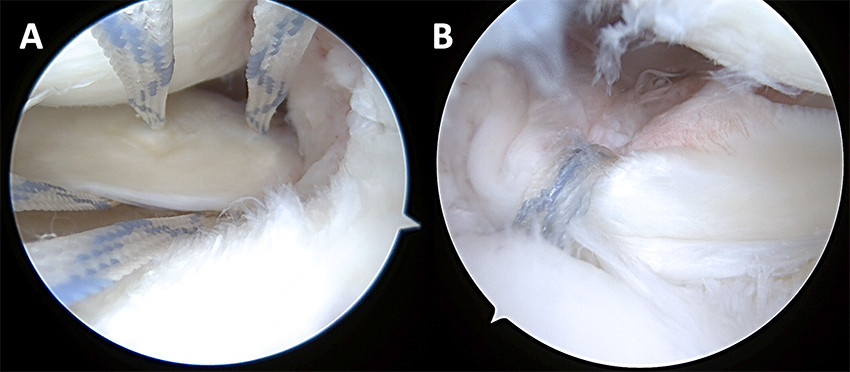

Traumatic meniscus and root tears should be treated with arthroscopic surgery with repositioning of the meniscus and fixation with various types of sutures (Figure 4). Degenerative root tears are amenable to surgery in the absence of definitive osteoarthritic changes in the articular cartilage. Postoperative rehabilitation protocols diverge depending on the type of tear and repair, but as a rule of thumb, crutches to reduce weight-bearing are recommended for six weeks along with physiotherapy-guided strength training. Squatting is allowed after three months, and sports and physical activities can be resumed after 5–7 months (29). Various healing rates have been described in the literature, with a meta-analysis of bucket-handle tears reporting a rate of 77 % (30). In the case of root tears, healing of up to 93 % has been shown after two years (31).